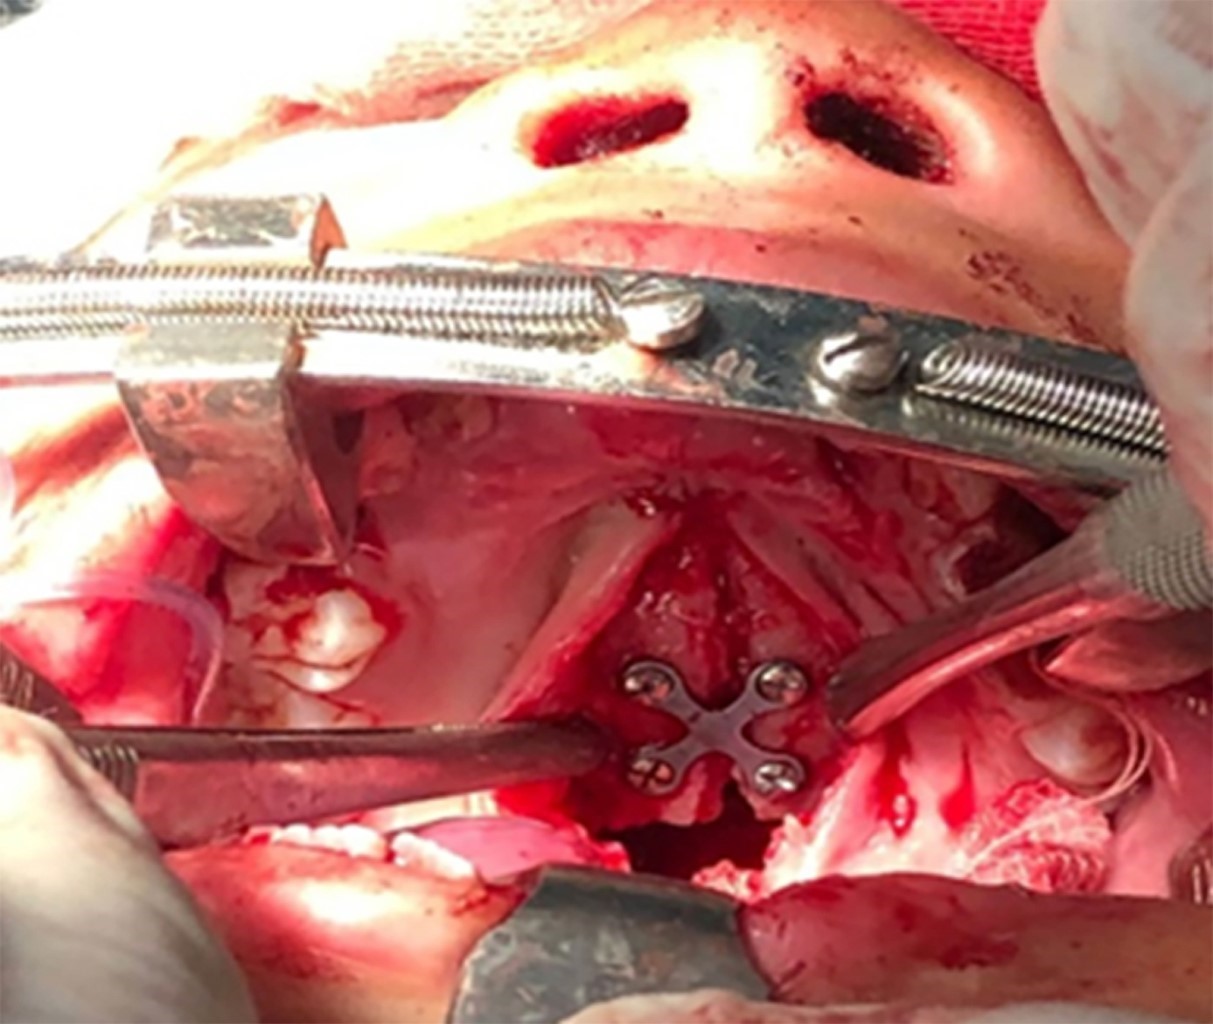

El tratamiento quirúrgico se realiza bajo anestesia general e intubación submentoniana (reducción cruenta y osteosíntesis), se realiza incisión en cola de ceja (Figura 4), diéresis por planos hasta llegar a plano óseo, reducción y fijación con material de osteosíntesis, incisión subtarsal y diéresis hasta llegar al plano óseo, reducción y fijación con miniplacas (Figura 5), incisión en fondo de surco vestibular bilateral, desprendimiento de colgajo mucoperióstico e identificación del trazo de fractura a nivel del hueso malar y maxilar superior. Con la ayuda del elevador de Palomeque (Figura 6) se desimpacta el tercio medio y se reducen las fracturas del tercio medio facial instalando placas rectas y en L: 1,5 y 1,3. Finalmente se reduce la fractura del paladar, desprendiendo la fibromucosa palatina y fijada con placa tipo X (Figura 7). La fractura NOE se reduce y se realiza cantopexia con aplicación de férulas artesanales. El procedimiento duro cinco horas sin complicaciones.

Figura 5

Figura 7